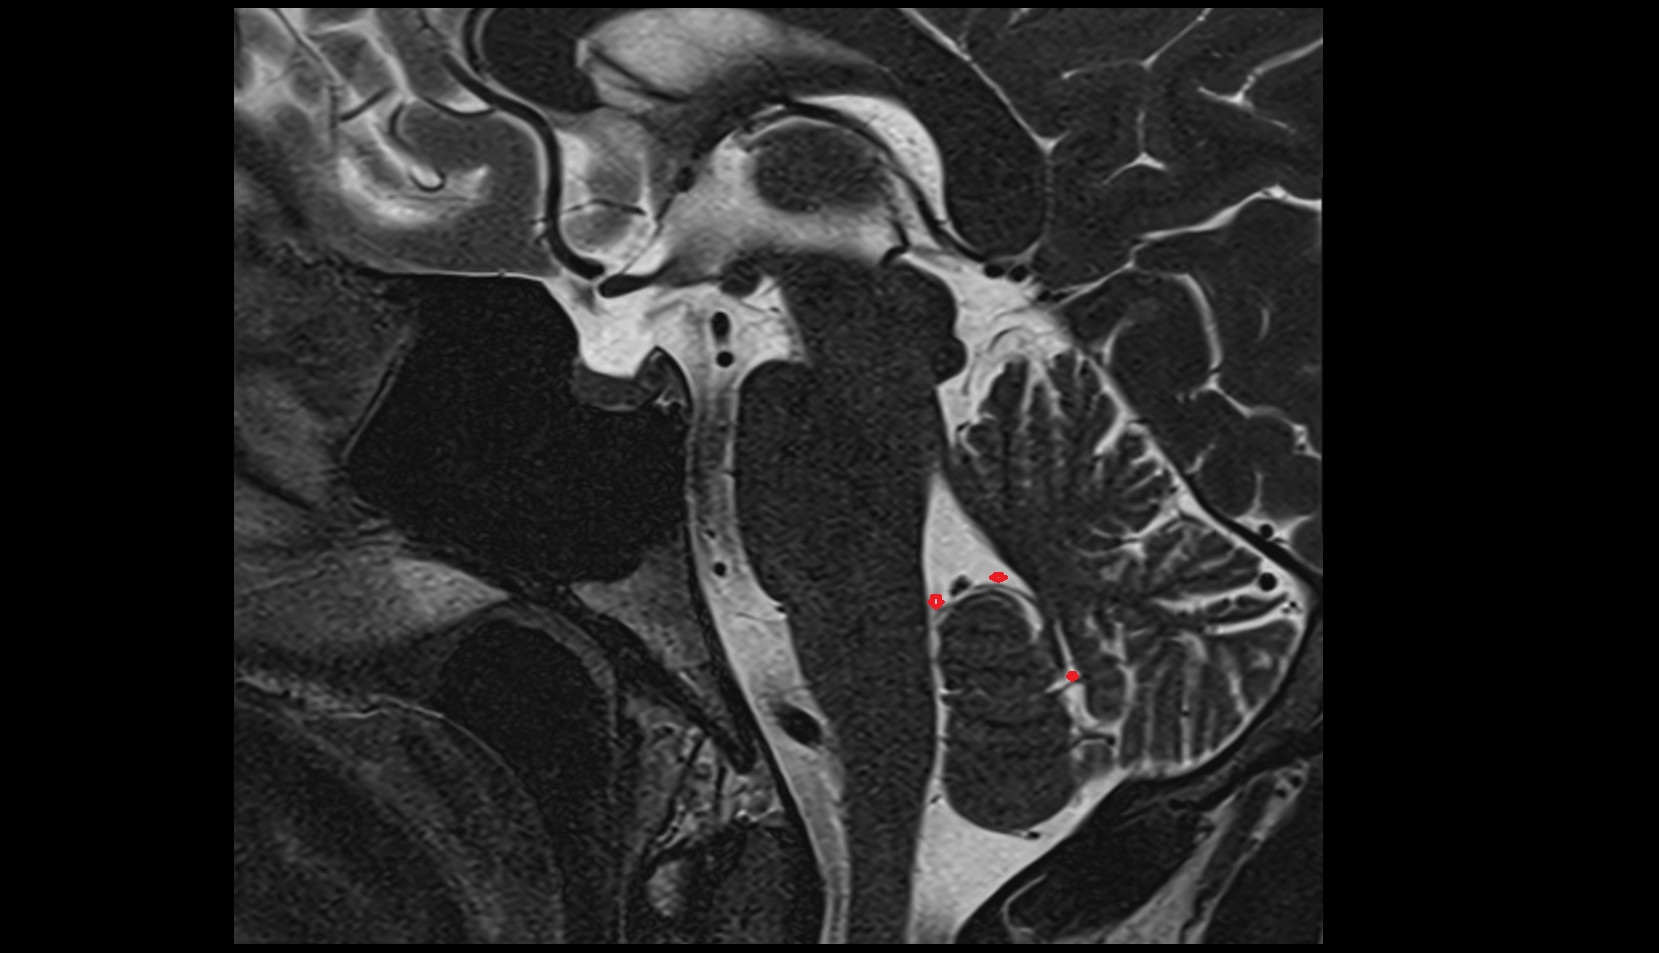

- Temporomandibular joint

- Mandibular condyle

- Mandibular fossa

- Articular disc of temporomandibular joint

- Articular eminence

- Superior head of lateral pterygoid muscle

- Inferior head of lateral pterygoid muscle